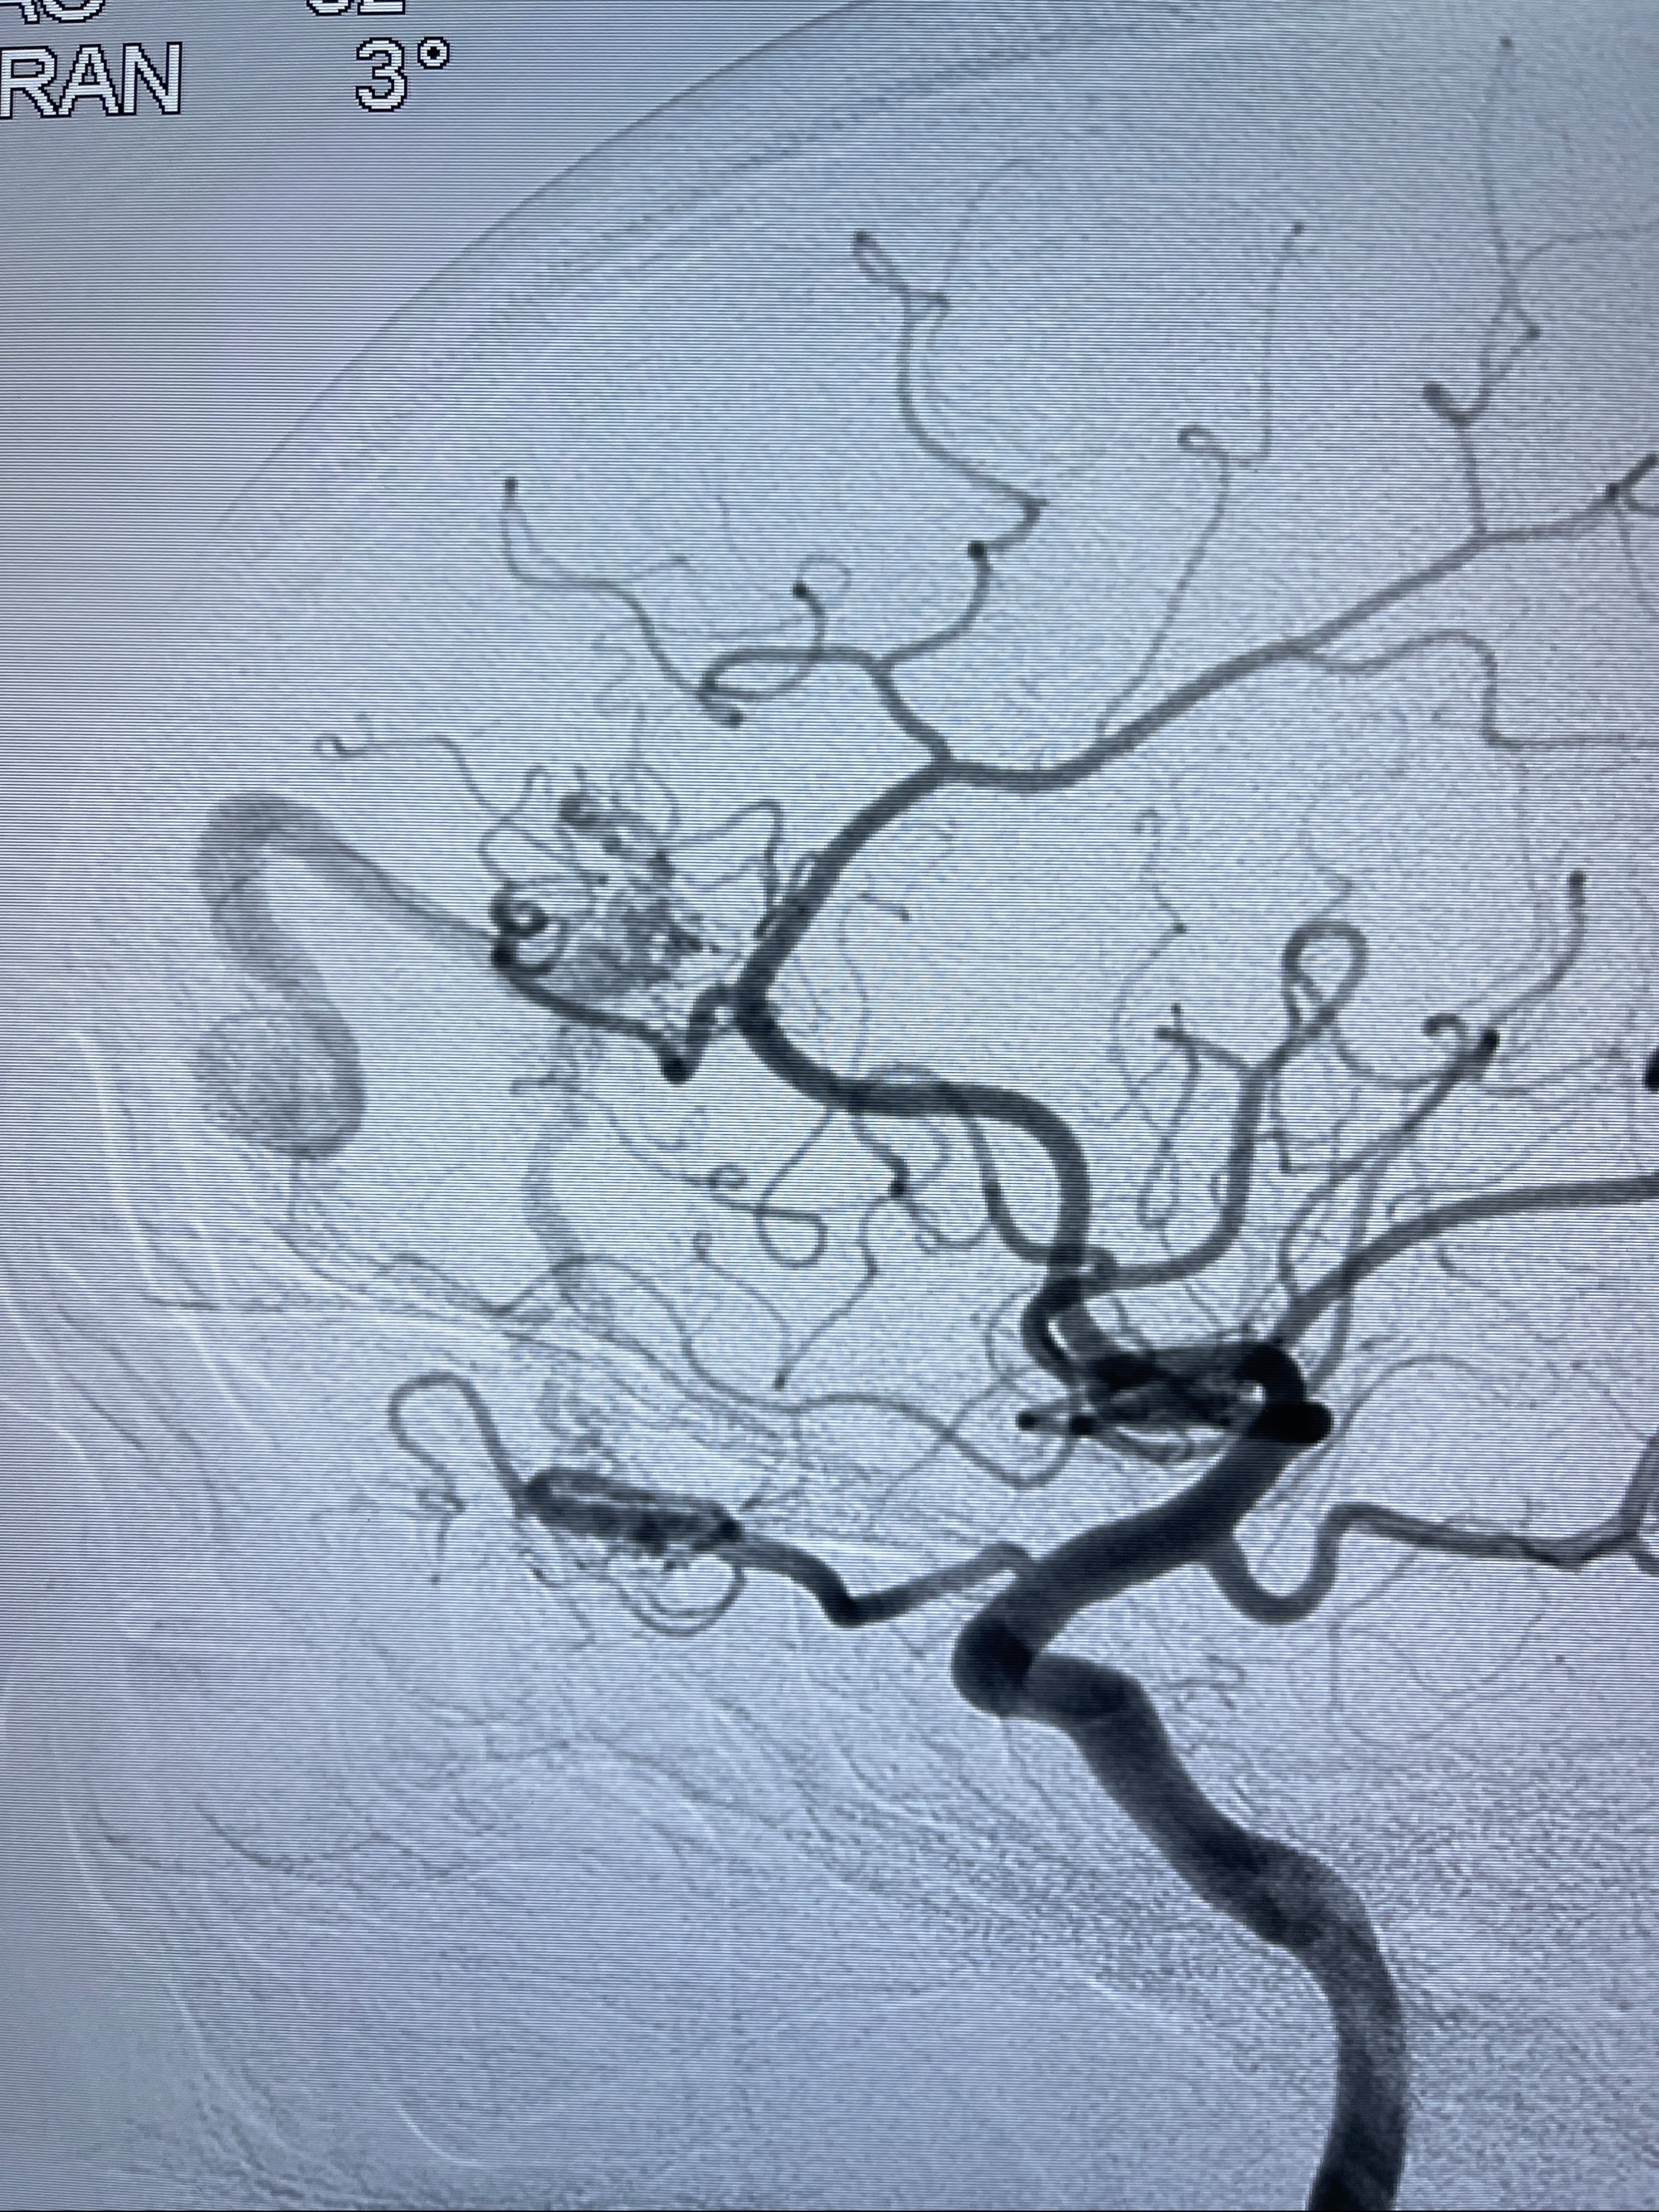

2023年8月21日]景德镇市第一人民医院脑血管造影检查,提示:主动脉弓、双侧颈总动脉、锁骨下动脉造影未见异常,左侧大脑前动脉静脉瘘。

2023-09-13全脑血管造影:前颅底硬脑膜动静脉瘘,供血动脉为双侧胼周动脉、眼动脉脑膜支,静脉向上矢状窦方向引流